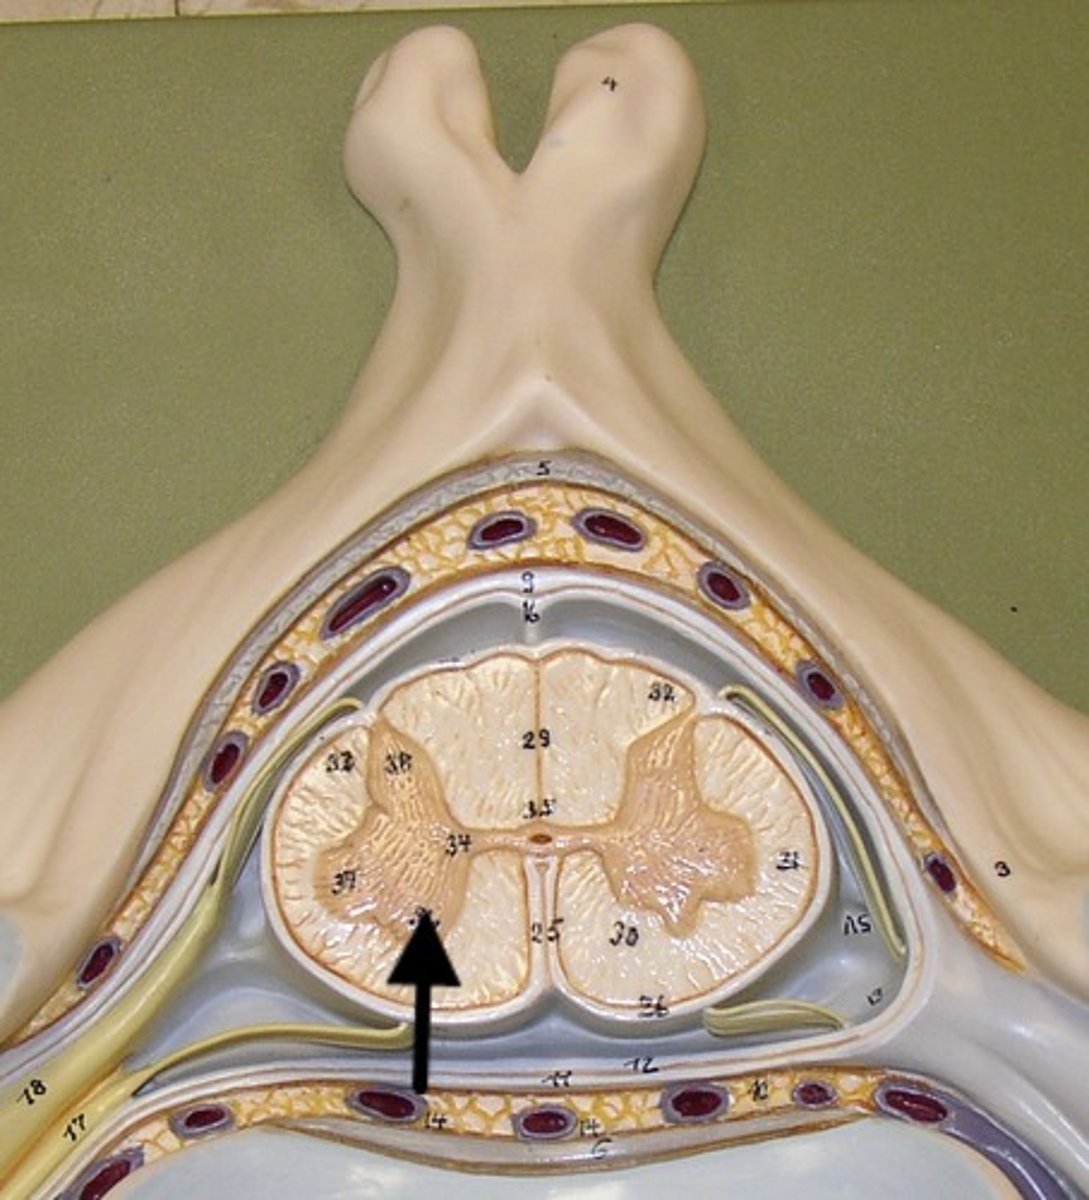

filum terminale

single thin thread of fibrous tissue at end of conus medullaris in the center that attaches to coccygeal ligament

posterior root

axons of sensory neurons

posterior root ganglion

anterior root

axons of motor neurons

spinal nerve

cauda equina

bundle